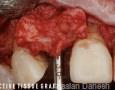

SOFT-TISSUE GRAFT:

Autograft: CTG

Surgery